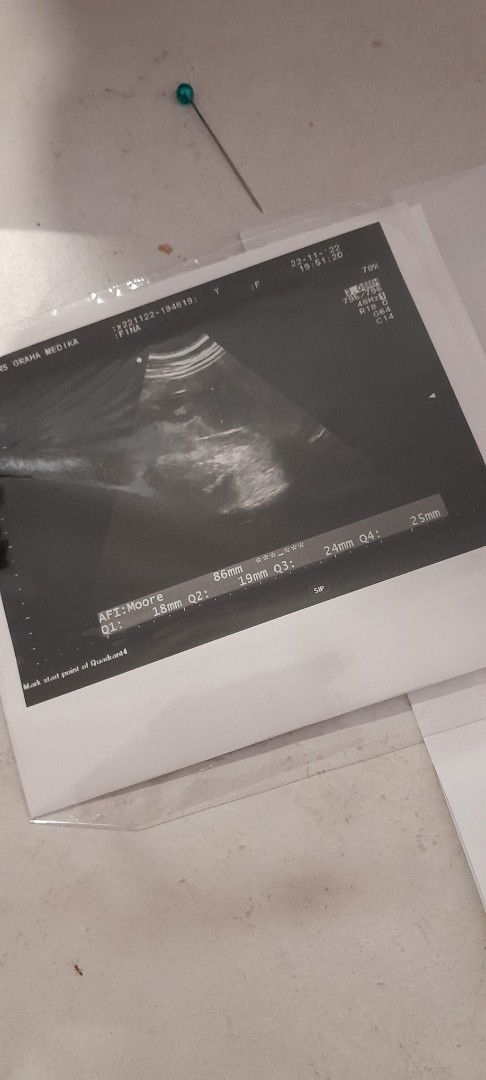

Halo bun, mau nanya nih. Kmren tgl 22 nov sy usg kan, trs trnyata setelah periksa sy di diagnosa mengalami oligohidramnion atau air ketuban sedikit. Dan minggu depan di suruh untuk kontrol lagi. Akhirnya saya cari2 artikel ttg oligohidramnion, trnyata pengukuran cairan menurut AFI itu normalnya 5-25 cm. Nah trs saya jumlahkan Q1-Q4 sesuai foto di usg jumlahnya msh 86mm atau 8,6cm kan ya bun. Bukannya itu normal ya? Tp knp dokter bilang kurang. Bukannya gamau percaya tp aku awam soal giniann. Tp kalo gk kontrol takut juga kalau utun kenapa2. Mungkin ada yg sama punya pengalaman seperti saya?#bantusharing #seriusnanya